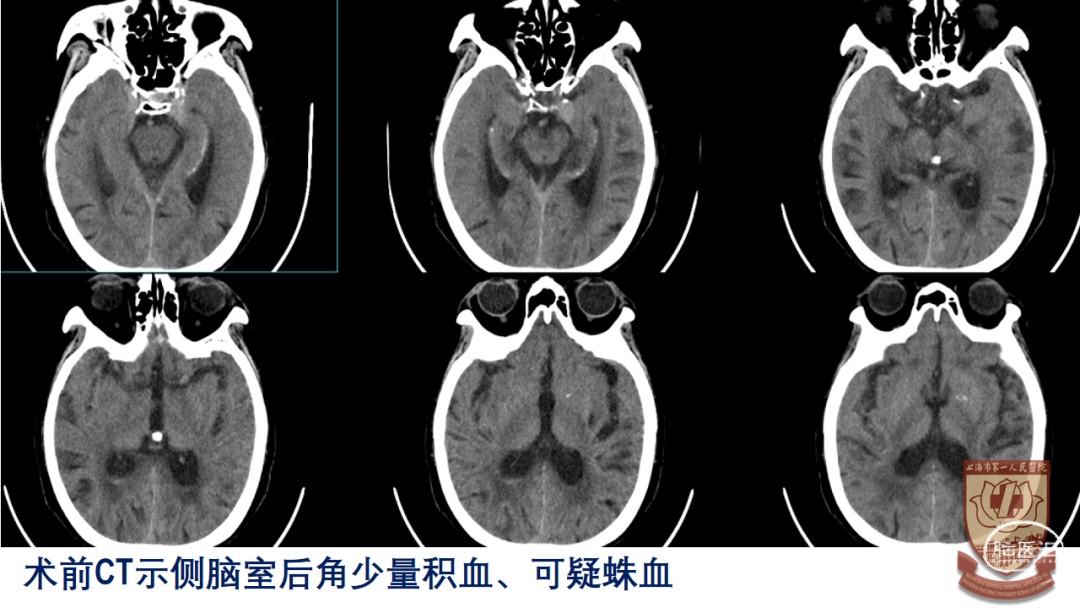

CT:双侧脑室后角少量积血,蛛网膜下腔出血可能